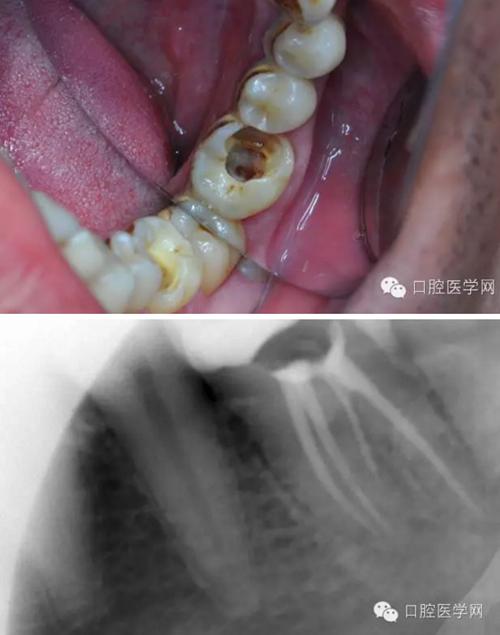

患者,肖某,男,32歲,#36慢性牙髓炎。遠(yuǎn)中舌根根尖1/3彎曲而且鈣化不通,我用盡辦法疏通了很久也沒到達(dá)WL,(我一直在幻想,要是有超聲系統(tǒng)該多好,可是現(xiàn)實(shí)很骨感,我們單位暫時還沒有超聲系統(tǒng)),后來我放棄了,最后的根充片顯示遠(yuǎn)中舌根充填物距根尖端2.84mm,屬于欠填范圍(根管內(nèi)充填物距根尖端2mm以上),其它三根根尖1/3鈣化相對沒那么嚴(yán)重,根充片顯示屬于恰填范圍(根管內(nèi)充填物距根尖端0.5~2mm)。歡迎網(wǎng)友們針對這個病例提出寶貴的建議!

9.png

10.png